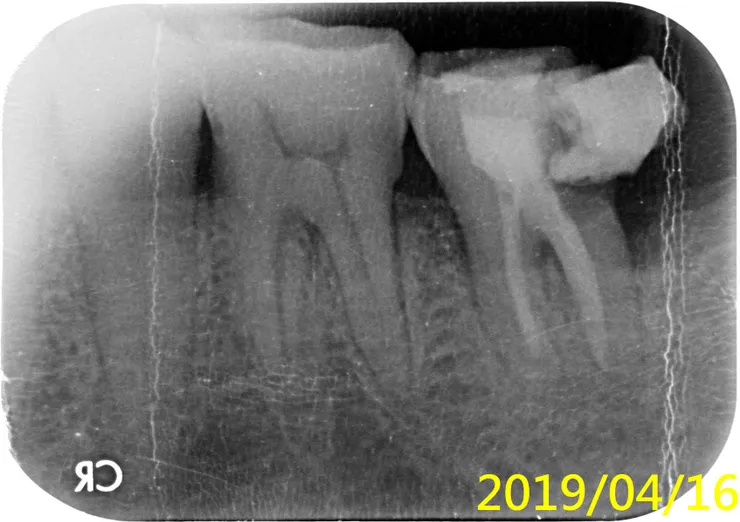

#38智齒拔完後,惡夢還沒結束,還要面對#37的根管治療(抽神經)

一年後,病人回來說,補的掉了

2018時我就已跟病人說的很清楚了,這裡就不贅言,直接引用張添皓醫師的文章說明『根管治療後,不做牙套,是多麼的危險,會導致前功盡棄(保留牙齒廢物利用,不要拔牙)』,何況他的情況,還不能直接做假牙,要先做『牙冠增長術』......所以,為了幫智齒擦屁股、收拾爛攤子,您看事後要付出多大的代價....

他後來當然就自動消失啦,去找願意幫他便宜處理的所謂良心牙醫啦,只不過,撐不到一年(才幾個月...),他就又回來找我啦(所以我才有這珍貴的歷史紀錄)....